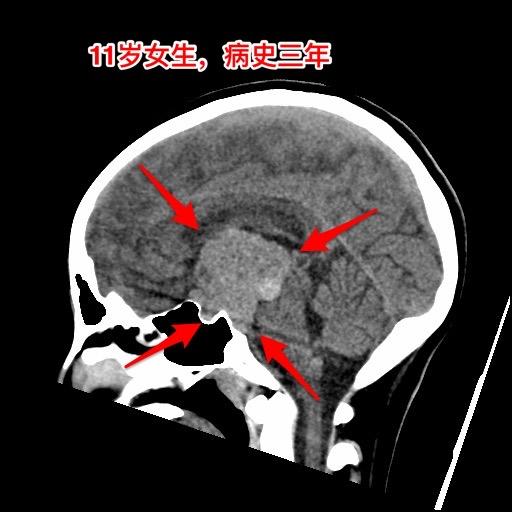

警惕小儿脑肿瘤。小孩子如果长了鞍区肿瘤,一般都会出现症状,一旦有了症状家长及医务人员就要足够重视,才能及时找到病因。 今天介绍的小孩子,肿瘤发现的就晚了。 11岁四川女孩子,因多饮多尿3年半,视力下降9个月,行走不稳、贪睡一个月发现鞍区肿瘤,急忙到北京来就医。 三年前开始出现多饮多尿症状,夜间上厕所好几次,到医院检查没有发现肾脏问题,就没有继续查找原因。 近两年身高增长缓慢,到医院化验显示生长激素缺乏,在当地医院注射生长激素治疗,没有查找生长激素